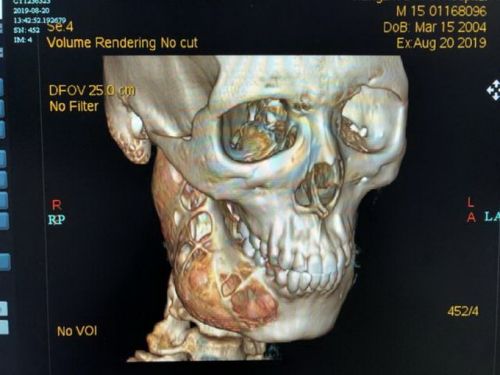

Tras una radiografía 3D los especialistas detectaron un ameloblastoma que provocó un agujero en la mandíbula inferior y, además, distintas lesiones en el hueso.

El ameloblastoma es un tumor benigno, poco frecuente y que se desarrolla generalmente en la mandíbula, cerca de los molares. Comienza en las células que forman el revestimiento del esmalte protector de los dientes, tiende a aumentar su tamaño lentamente y causa anormalidades en la cara y mandíbula. Además, por la proliferación anormal de las células, se infiltra y destruye los tejidos óseos.